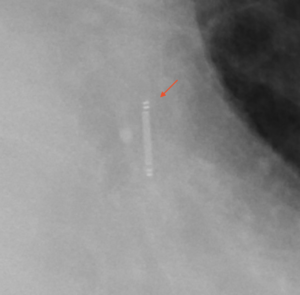

CXR CARDIOMEMS INSET

May 1, 2021